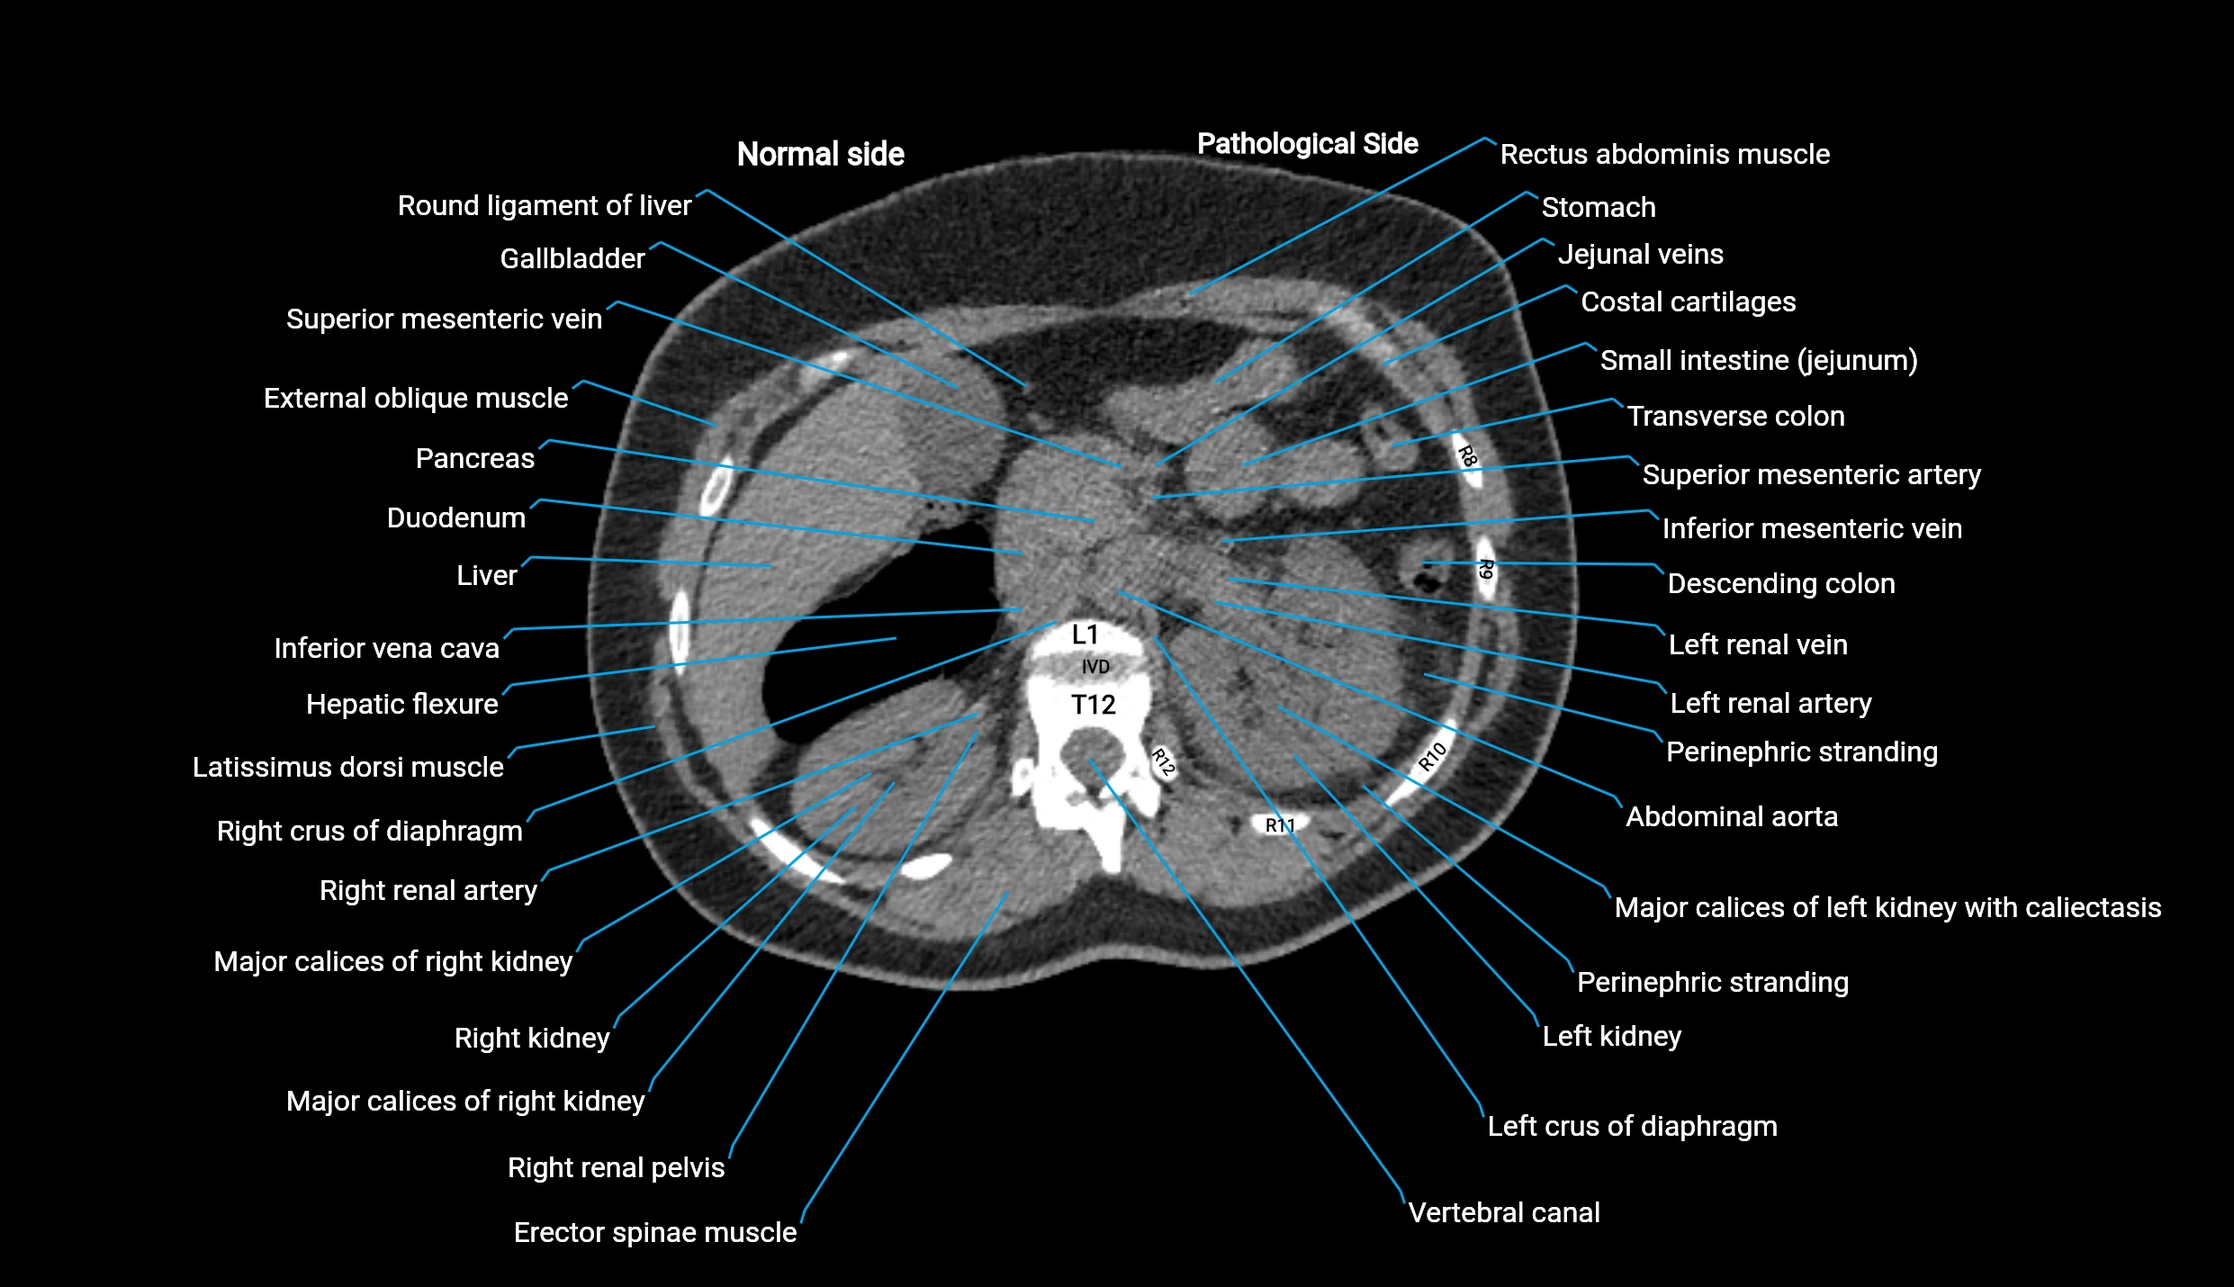

CT image

image